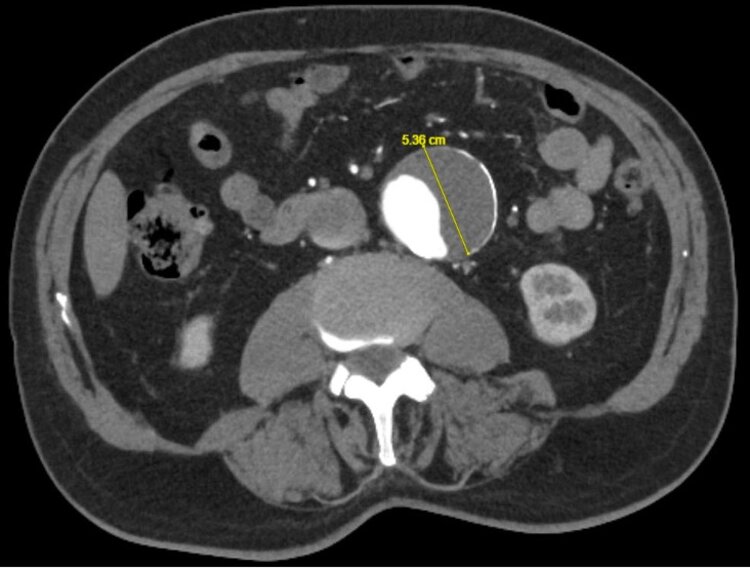

Die Diagnosestellung erfolgt in der Regel per Ultraschall, ist oftmals aber auch ein Zufallsbefund, so dass die Erstdiagnose auch in einem CT oder Kernspin erfolgen kann (Abbildung 1 a–c). Meistens jedoch wird zuerst mittels Ultraschall geschaut und ggf. im Anschluss eine CT- oder Kernspinuntersuchung durchgeführt um die genaue Grösse und Ausdehnung festzustellen.

So ist z.B. ein Bauchaorten-Aneurysma unter 5 cm primär konservativ zu behandeln mit dem Ziel ein weiteres Wachstum zu verhindern. Dies erfolgt mittels Einstellung eines erhöhten Blutdrucks (Ziel Blutdruck systolisch (oberer Wert) < 140 mmHg), Statin Einnahme und Blutplättchenhemmer. Der Patient sollte zudem nicht schwerer als 5 kg heben, da hierdurch ein weiteres Aneurysmawachstum gefördert wird.

Bei einem Bauchaortenaneurysma über 5 cm (Frauen) bzw. 5.5 cm (Männer), sollte über ein operatives oder minimalinvasives (endovaskuläres) Verfahren nachgedacht werden. In Einzelfällen ist es auch bei einem kleinerem Durchmesser als 5 cm notwendig operativ oder interventionell zu behandeln.